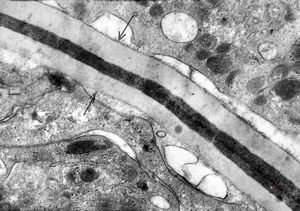

M,10y. | herpes virus - herpetic encephalitis